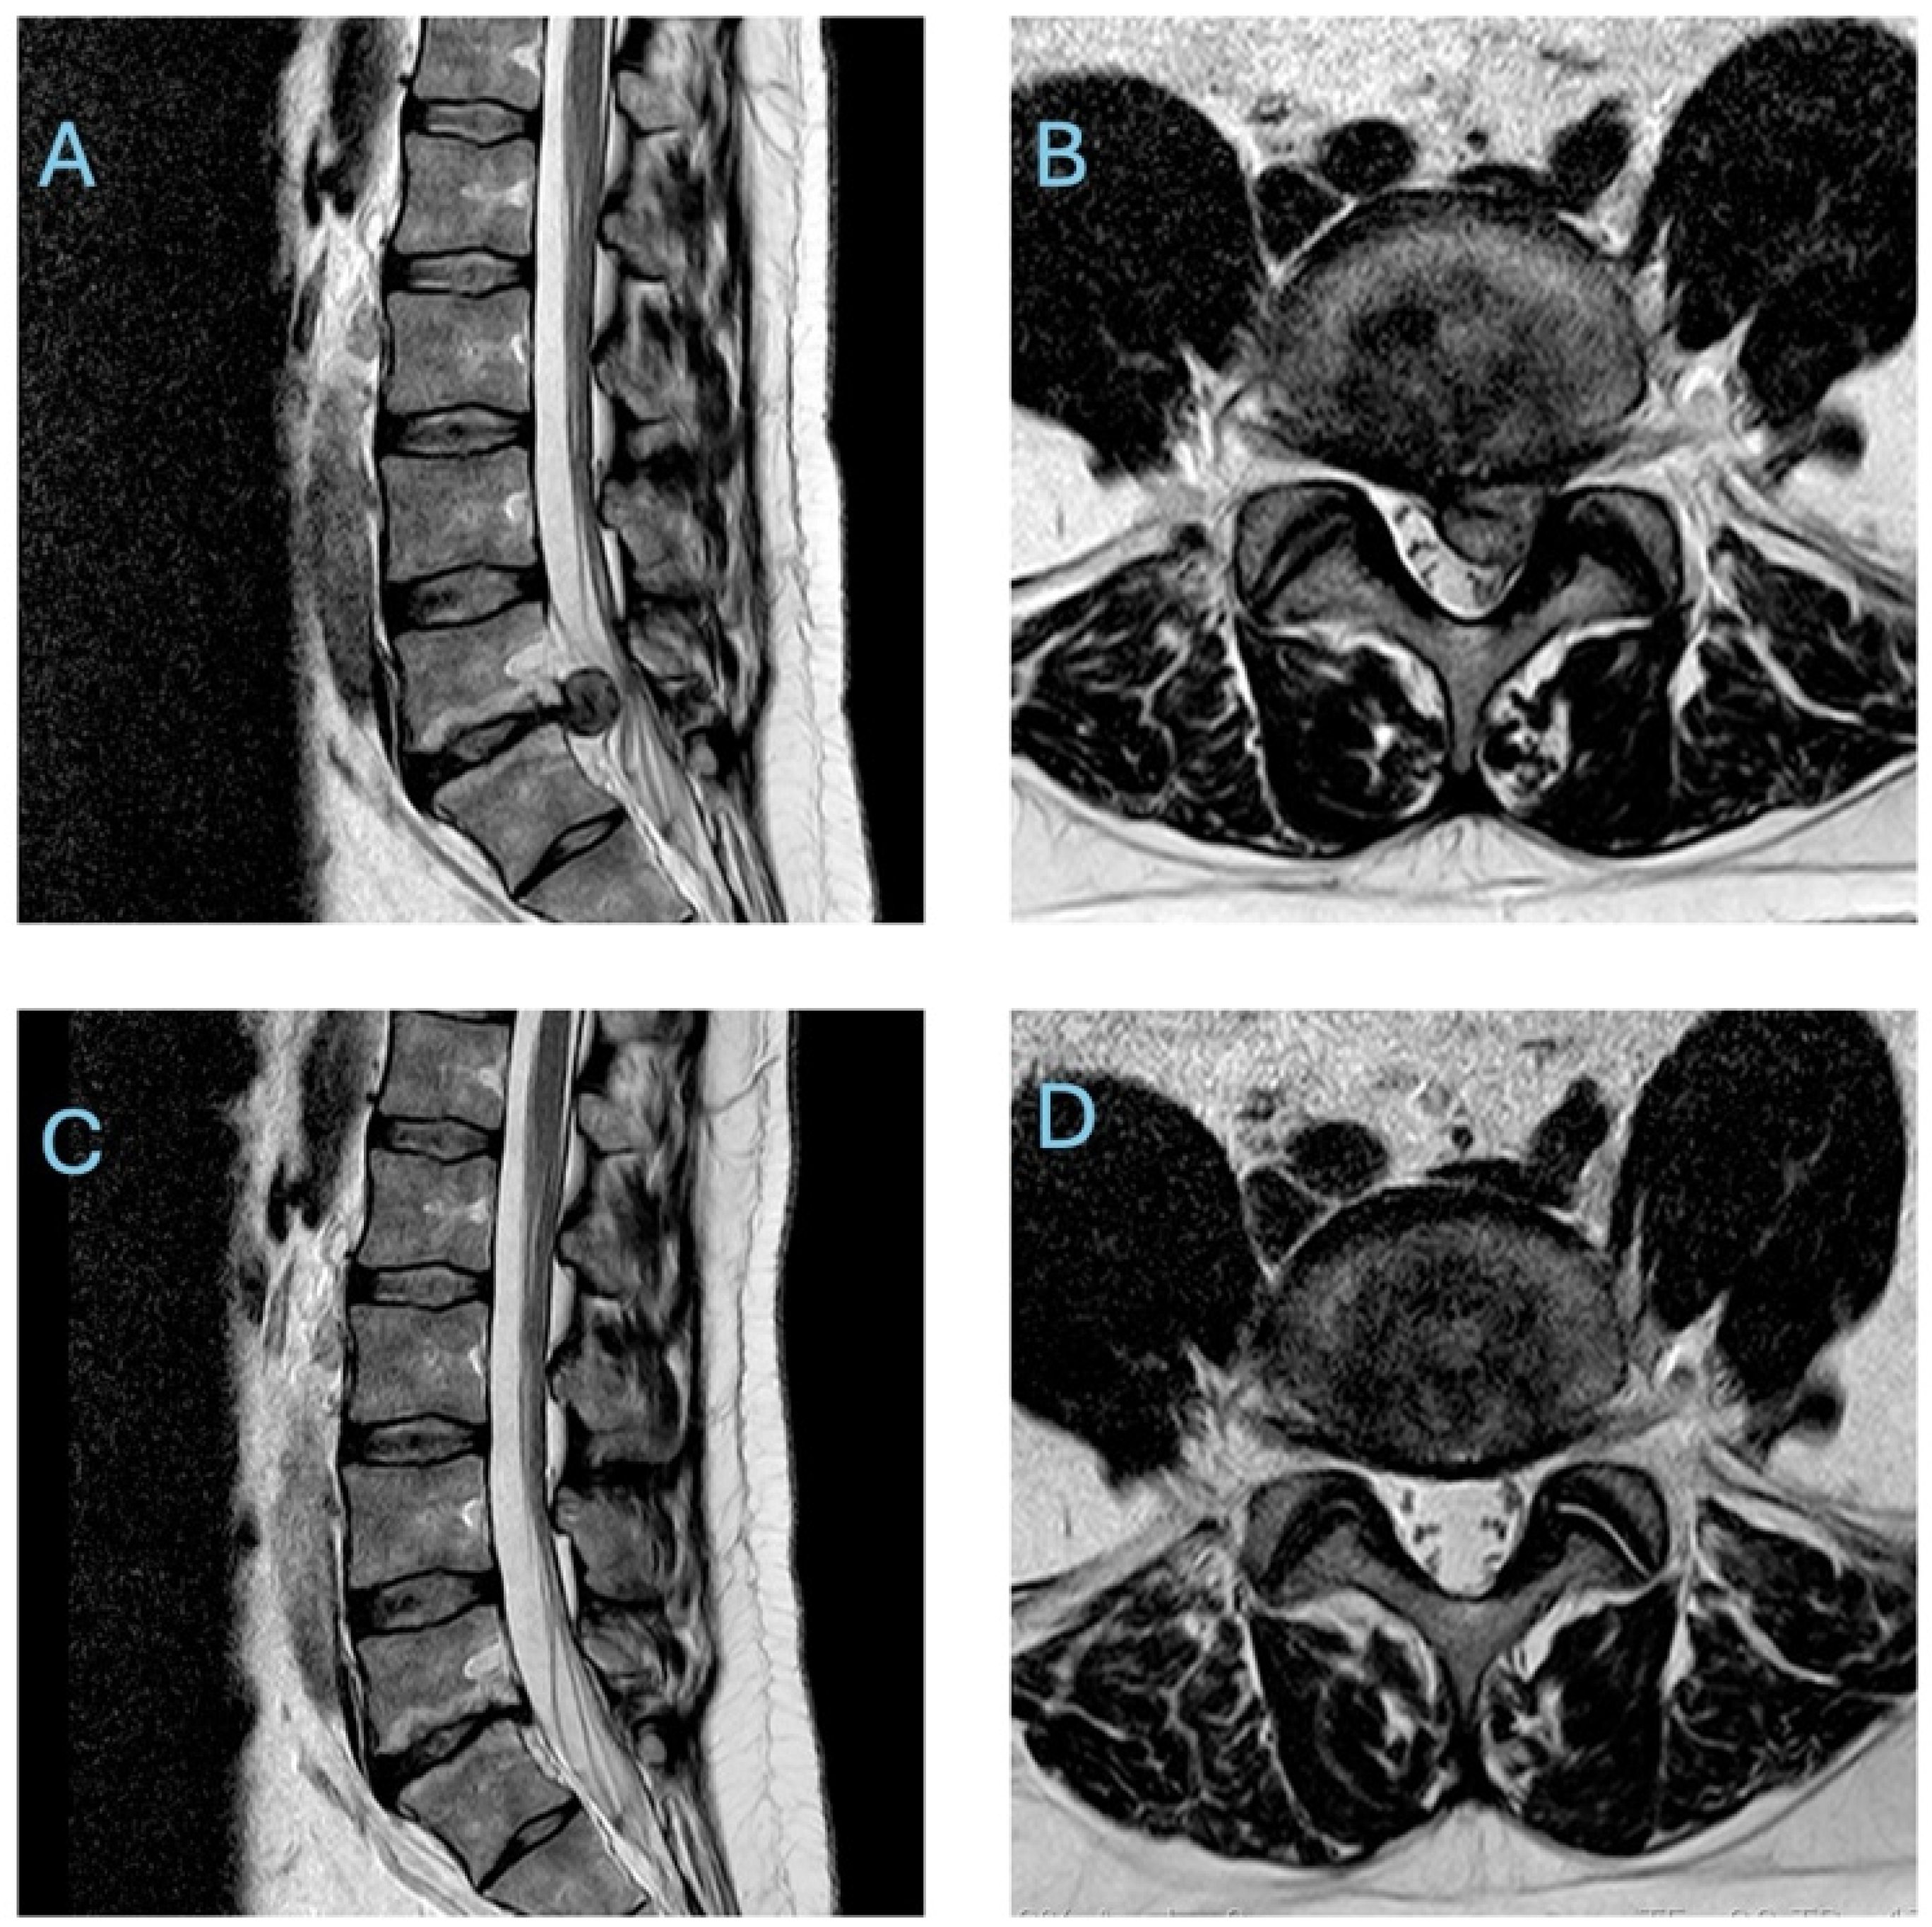

One of the key biological explanations for these favourable outcomes is the phenomenon of spontaneous disc herniation resorption (sometimes termed spontaneous “disappearance” or “regression” of the herniated nucleus pulposus). First noted in imaging studies several decades ago, spontaneous resorption refers to a process whereby the extruded or protruded disc fragment diminishes in size or even vanishes on follow-up imaging without any surgical removal. This correlates with the relief of nerve root compression and subsequent alleviation of radicular pain. In fact, systematic reviews have estimated that roughly half to two-thirds of herniated lumbar discs show at least partial spontaneous shrinkage on serial scans during conservative treatment, with some studies reporting complete resolution of the herniation in a significant subset of patients. It is important to note that clinical symptom improvement and radiological disc regression, while often correlated, do not necessarily occur simultaneously, and improvement in pain or function may precede, parallel, or lag behind MRI-confirmed reduction in disc size. Such evidence has provided a strong rationale for initially deferring surgery in many cases, as the body may effectively “heal” the disc extrusion over time. As illustrated in Figure 1, follow-up MRI scans of patients managed conservatively often demonstrate dramatic reduction or complete disappearance of the herniated disc fragment, corresponding to the resolution of nerve compression and symptoms [2,5,6].

Figure 1. T2 weighted MRI images of a lumbar disc herniation demonstrating spontaneous resorption. The sagittal (A) and axial (B) views show a large disc extrusion compressing neural elements before treatment. After five months of conservative management, follow-up sagittal (C) and axial (D) scans of the same patient show complete disappearance of the herniated disc material, with relief of neural compression.